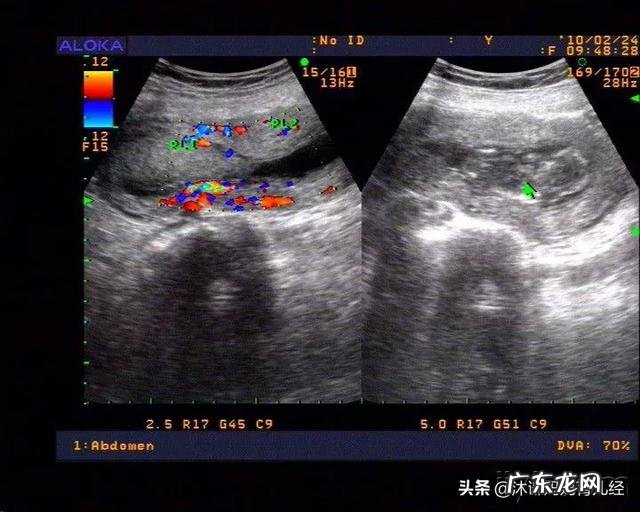

文章插图

第三、HCG值出现下降

一般医生会通过B超、HCG检查综合判断 。若孕妈妈出现了上述症状,产检医生会通过B超,查看你的孕囊形态是否正常、胎心有没有搏动、以及查看子宫和宫颈的状况来诊断胚胎发育 。

另一方面在孕6~8周的时候,HCG的水平会以每天66%的速度增长 。如果测定孕妈妈血液中的HCG水平,在48小时(2天)增长速度小于66%,就表明胚胎发育不是很好,需要继续观察!